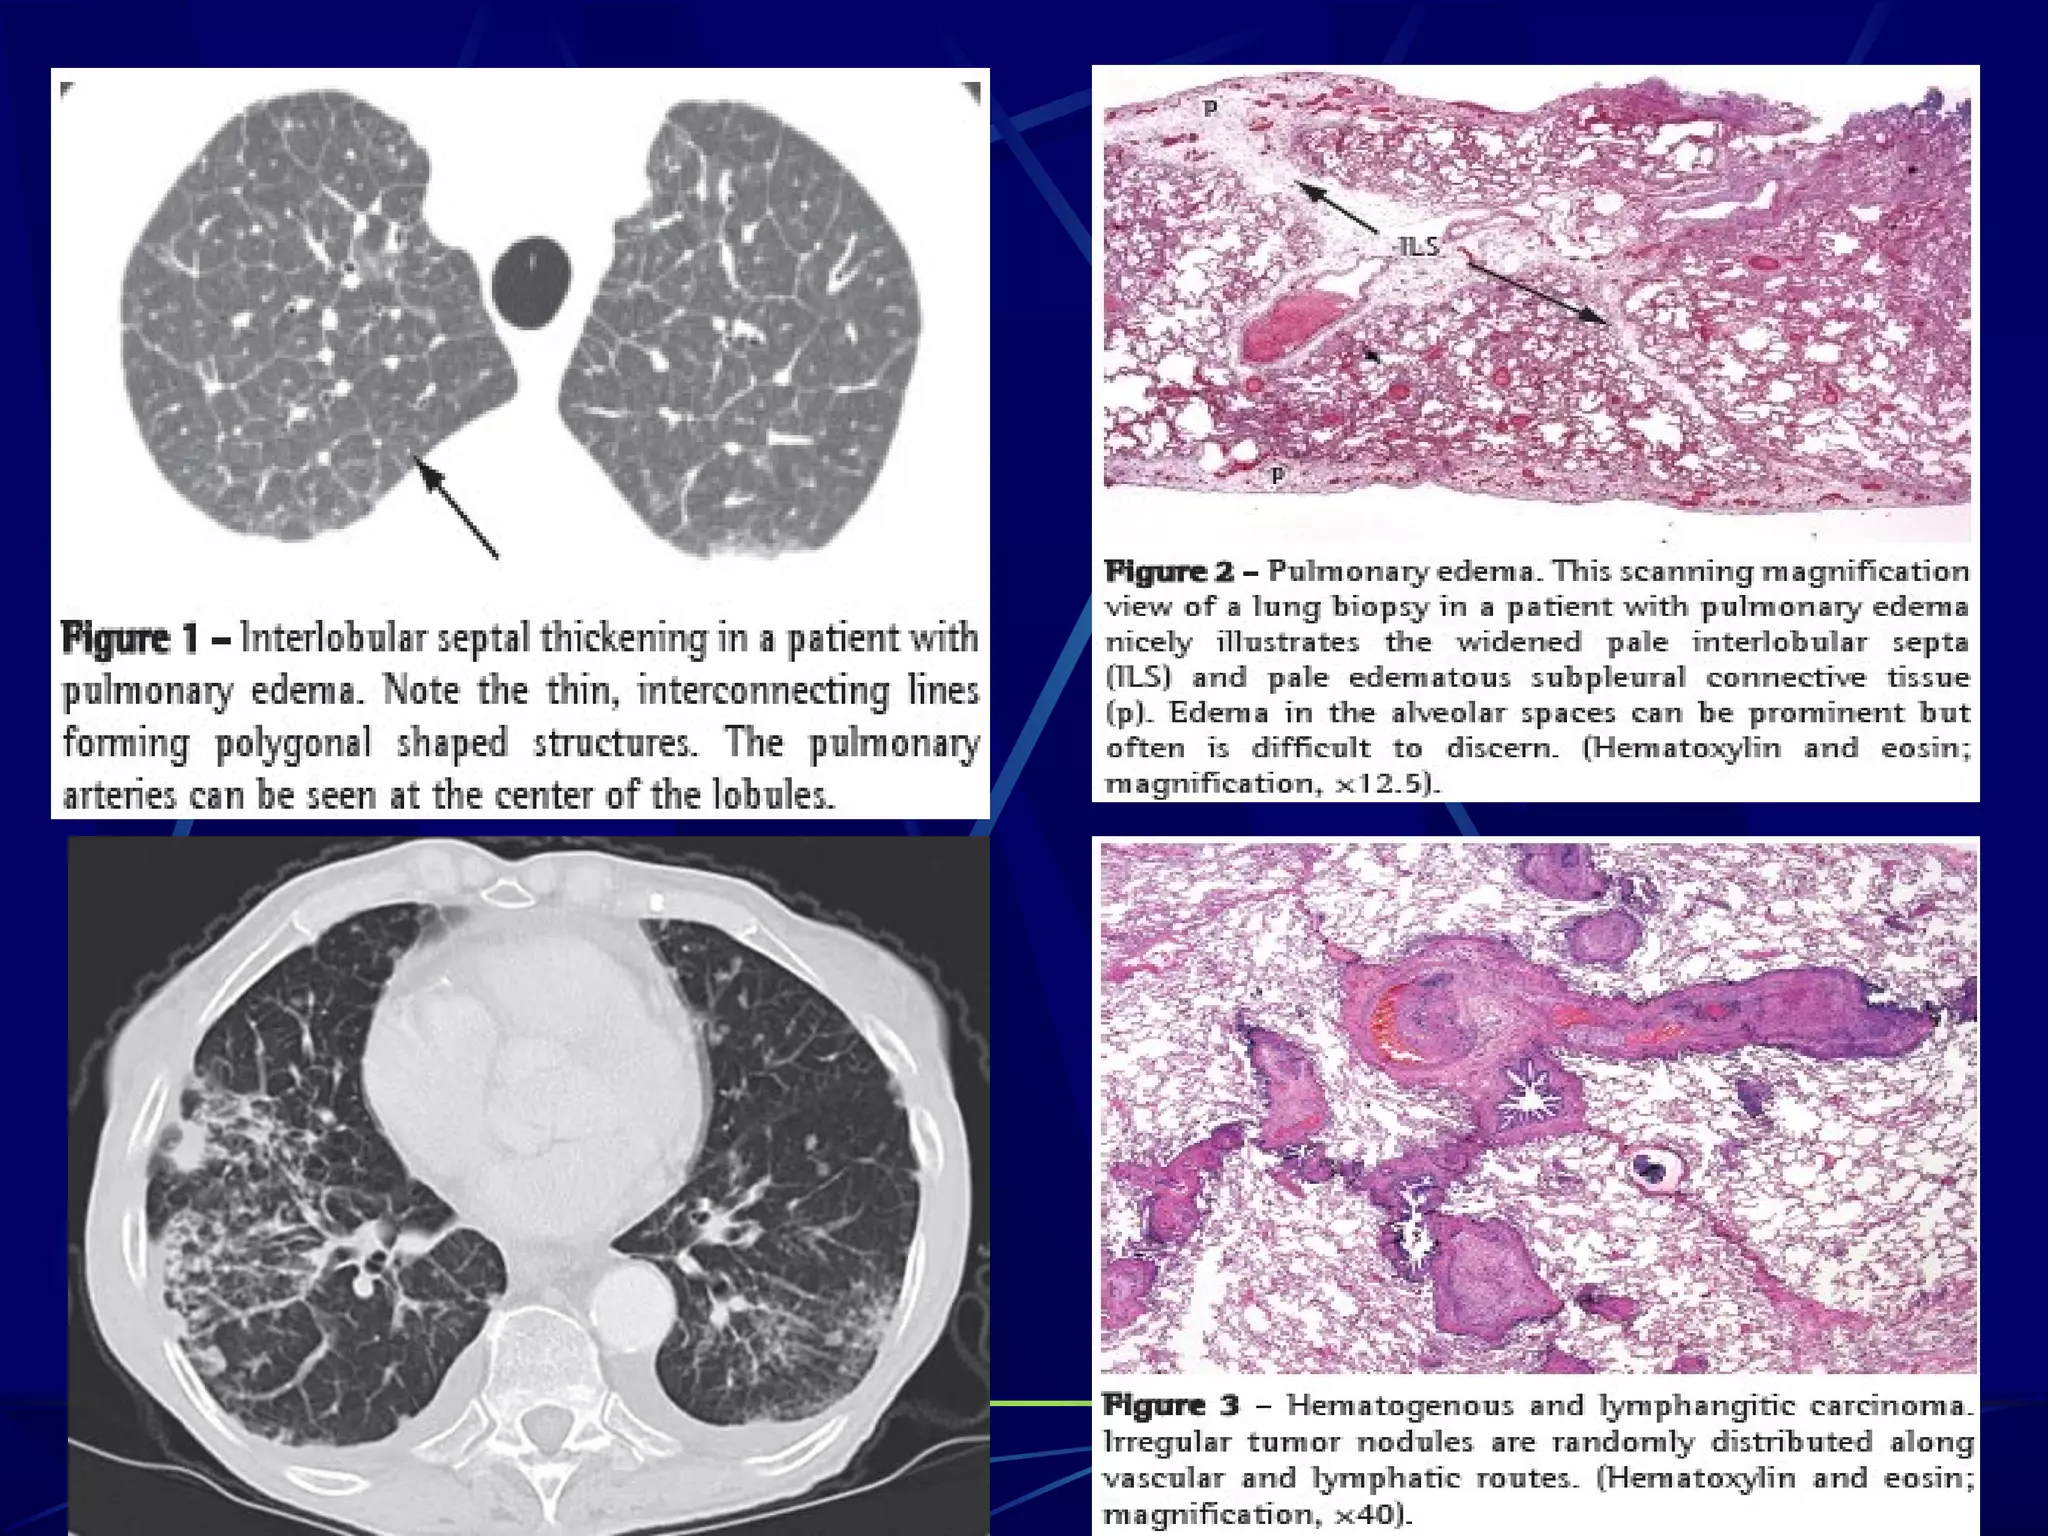

Cardiogenic pulmonary edema (CPE) is defined as pulmonary

edema due to increased capillary hydrostatic pressure secondary

to elevated pulmonary venous pressure. CPE reflects the

accumulation of fluid with a low-protein content in the lung

interstitium and alveoli as a result of cardiac dysfunction .

CARDIOGENIC PULMONARY EDEMA

Cardiogenic pulmonary edema(CPE) is defined as pulmonary edema due to increased capillary hydrostatic pressure secondary to elevated pulmonary venous pressure. CPE reflects the accumulation of fluid with a low-protein content in the lung interstitium and alveoli as a result of cardiac dysfunction .